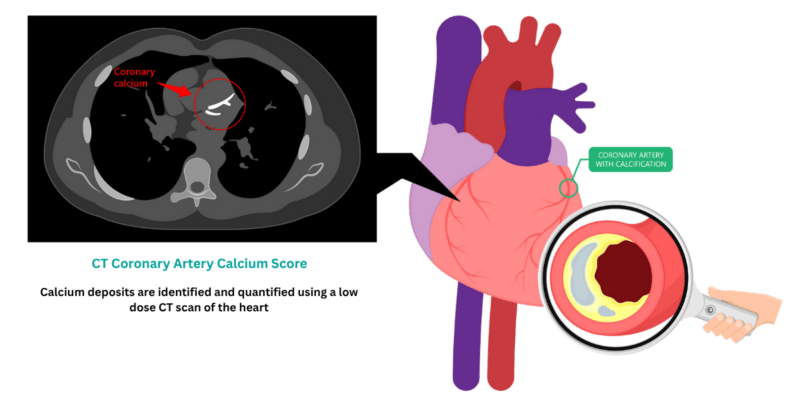

Our personalised heart health check starts with a CT Coronary artery calcium scan.

This is a dedicated low-dose CT scan of the heart which looks for deposits of calcium in the arteries that supply blood to the heart muscle.

From this scan, a score is calculated, which is a measurement of the build-up of calcium in the coronary arteries, and can be used to assess for the presence of early heart disease and heart attack risk.